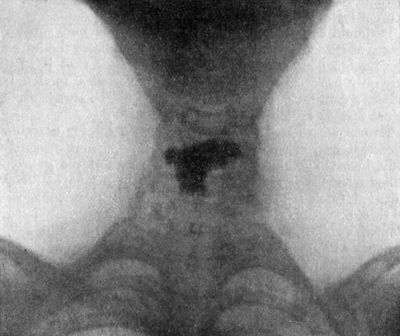

| 213. | Radiogram of Child's Thorax showing Spindle-shaped Shadow at Site of Pott's Disease of Fourth, Fifth, and Sixth Thoracic Vertebræ | 437 |